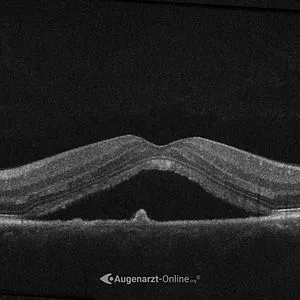

Die zentrale seröse Chorioretinopathie ist eine Erkrankung der Makula, also jenes Bereichs der Netzhaut, der für scharfes Sehen verantwortlich ist. Dabei sammelt sich Flüssigkeit unter der Netzhaut an.

Ursache ist meist eine Störung im Zusammenspiel von retinalem Pigmentepithel und Aderhaut. Die Folge ist eine kleine Abhebung der Netzhaut im Zentrum, wodurch das Sehen verschwommen oder verzerrt wirkt.

Wie wird eine CRCS diagnostiziert? +

Die Diagnose erfolgt durch Spaltlampenuntersuchung des Augenhintergrunds und vor allem durch hochauflösende OCT-Bildgebung, mit der die Flüssigkeit unter der Netzhaut sichtbar gemacht wird. Bei Bedarf ergänzt die Fluoreszenzangiographie die Diagnostik, um die genaue Leckagestelle zu lokalisieren.